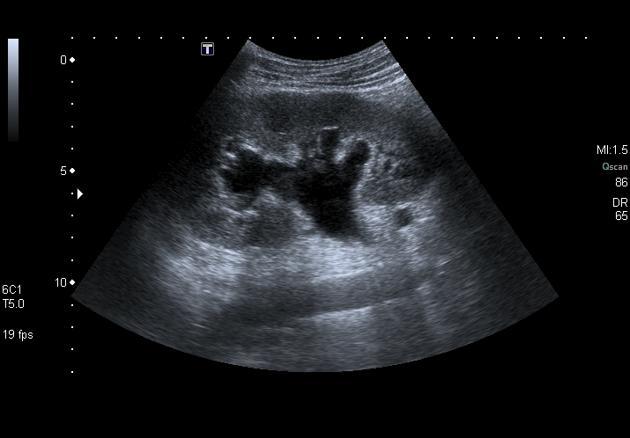

Bilan d’insuffisance rénale chronique: que voit-on?

Multiples kystes et gros rein: probable polykystose rénale